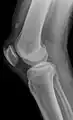

Quadriceps tendon rupture in plain X-ray

Quadriceps tendon rupture in plain X-ray: Incomplete rupture with haematoma in tendon.